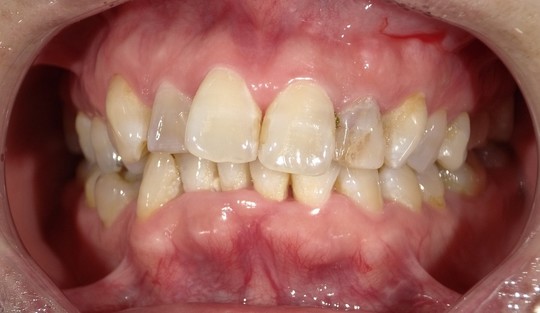

年齢:70代女性

治療内容:向かって右上の真ん中から2番目の歯で、保険の修復物の不適合を主訴でいらっしゃいました。

治療期間/通院回数:4回

費用:コア 17,600円

ジルコニアクラウン 194,500円

合計 212,100円 ※2025年7月現在の価格